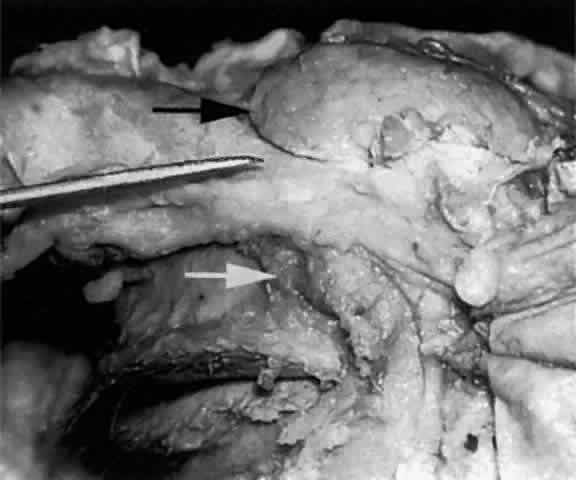

The main lacrimal gland resides in the superotemporal orbit, partially within a shallow bony fossa in the lateral angular process of the frontal bone (fossa glandula lacrimalis). The gland is situated between the eyeball below and the curved orbital wall above, giving it a somewhat compressed and curved shape. It may extend inferiorly to the lateral canthal tendon. The lateral horn of the levator aponeurosis crosses the gland anteriorly, separating it into a larger superior or orbital lobe and a smaller inferior or palpebral lobe (Fig. 2). The division is incomplete because the larger orbital lobe is connected to the smaller palpebral lobe posteriorly by a bridge of glandular tissue, draining tubules, and Müller's muscle, which is attached to the underside of the levator muscle and aponeurosis. The lacrimal gland is surrounded by fibrous tissue that is attached superiorly to the periosteum of the frontal bone and inferiorly to the orbital portion of the zygomatic bone.1

Fig. 2. With the roof and lateral wall of the left orbit removed, this cadaver dissection demonstrates the orbital lobe (black arrow) and the palpebral lobe (white arrow) separated by the lateral horn of the levator aponeurosis (pointer).

The almond-shaped orbital lobe (see Fig. 2) represents approximately 65% to 75% of the gland and measures 20 mm long × 5 mm thick × 12 mm wide.2 Its sharp anterior border rests behind the superior orbital rim and is covered by the orbital septum (Fig. 4) and a portion of the temporal aspect of the central preaponeurotic fat pad (Fig. 5). Posteriorly, its rounded border is supported by a large superotemporal fat pad at the plane of the posterior pole of the globe.3 The convex superior surface is suspended from the periorbita of the lacrimal gland fossa of the frontal bone. The inferior border is convex and attached to the sheath of the levator aponeurosis. Its lateral border is smooth and convex in contour with the bony fossa.

Fig. 4. The sharp anterior border of the left lacrimal gland (black arrow) rests behind the orbital septum (pointer), which in this cadaver has been reflected anteriorly.